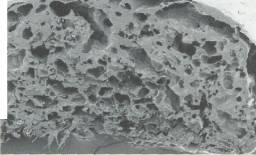

Yapay karaciğer oluşturmak, teknik açıdan oldukça güç. Poliüretan köpük iskelet kullanan bilim adamları yapay karaciğer oluşturabiliyorlar. Köpük içine yerleştirilen karaciğer hücreleri, mikrokümeler oluşturuyor. Elde edilen üç boyutlu yapay karaciğer vücut dışında 10 gün süreyle işlev görüyor. Karaciğer yetmezliği olan domuz ve farelere yerleştirilen bu yapay karaciğerler oldukça iyi sonuçlar verdi. Bilim adamları, deney aşamasındaki köpük karaciğerleri daha da geliştirerek, insanlarda kullanımı için çalışıyorlar.

Bu projede, biyobozunur biyopolimerler üzerine yerleştirilen karaciğer hücrelerinin çoğalmaları, dokusal organizasyonu tamamlayarak işlevsel bir yapay karaciğer oluşturmaları amacıyla, hücre kültürü (in vitro) ve canlı hayvan deneylerinin (in vivo) gerçekleştirilmesi hedeflenmekte. Hücrelerin elde edilmesi ve hayvan deneyleri için, bir laboratuvar deney hayvanı olan Sprague-Daw-ley sıçanları kullanılıyor.

Hedefe varmak için birbirinden farklı üç alanda deneyler yapılıyor. Bunlardan biri, biyobozunur biyopolimerlerin oluşturulması. Bunlar, üzerine eklenen sağlıklı hücrelerin tutunup çoğalması için bir destek, iskelet işlevi üstleniyor ve hücrelerin çoğalıp istenen organın hacmi ve işlevine erişme sürecine paralel olarak, vücutta reaksiyon yaratmayan küçük moleküllere ayrışarak ortadan kalkıyorlar. Projede bu biyopolimerler, dünyada da bu amaçla çok kullanılan laktik ve glikolik asit monomerleriyle oluşturuluyorlar; ancak, hücrelerin özgün olarak bu yapıya tutunmalarını sağlayacak molekülleri de bu polimerle-re katmak yoluyla, bu çalışmalar bir ileri aşamaya taşınmış durumda.